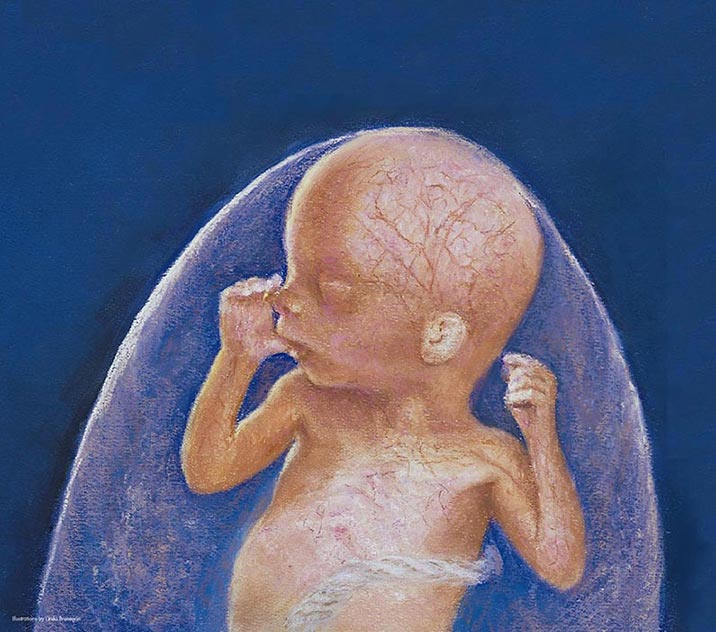

what does a 2 month old fetus look like

Posts: what does a 2 month old fetus look like